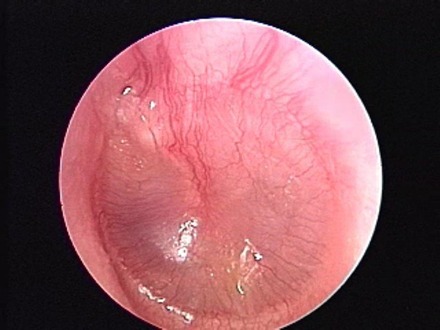

Otitis Media with Effusion (OME), commonly known as glue ear, is a condition where fluid collects in the middle ear without signs of acute infection. It is one of the most common causes of hearing difficulty in children, but it can also affect adults.

What is Otitis Media with Effusion?

The middle ear is an air-filled space behind the eardrum that helps transmit sound. Normally, it is ventilated by the Eustachian tube (a small canal connecting the ear to the back of the nose). When this tube does not function properly, fluid accumulates in the middle ear, leading to reduced hearing.